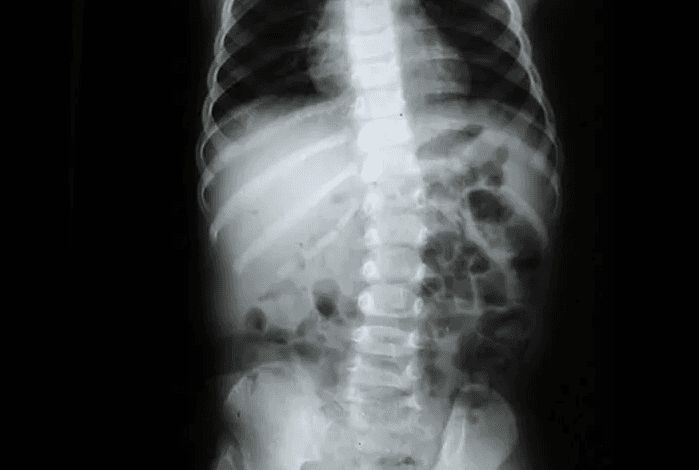

Telefonla konuşmanın iletişim açısından öneminin çok büyük olduğunu ama aşırıya kaçmanın sağlık tehditleri yarattığını kaydeden Prof. Dr. Özateş, "Boyundaki hem kas yapısı hem de kemik yapısını bozabiliyor, bunların fonksiyonlarını engelliyor. Muhtemelen ileriki yıllarda da ciddi bir kireçlenme artışı olacağını tahmin ediyoruz. Akıllı telefonlar postür bozuklukları, duruş anormallikleri ve buna bağlı olarak gelişen baş ve boyun ağrılarına yol açtığı gibi skolyoz dediğimiz omurganın eğriliklerine de neden olabiliyor. Son yıllarda gençlerde skolyoz çok görmeye başladık. 15-25 yaş arası gençlerde cep telefonlarının vücudunun doğal pozisyonunun dışında aşırı bir şekilde kullanılması neticesi o bölgelerde kemik yapılarının dizilimi bozuluyor, kas yapılardaki gerginlikler sonucu da sağlığı tehdit eder hale geliyor" ifadelerini kullandı.